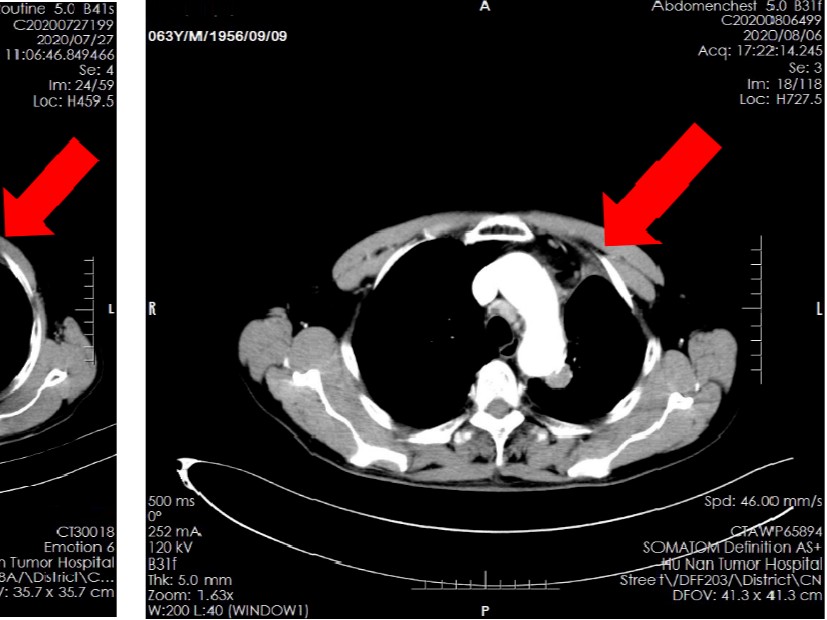

罗米地辛、阿扎胞苷、地塞米松和来那度胺联合治疗复发难治T细胞淋巴瘤的I期研究